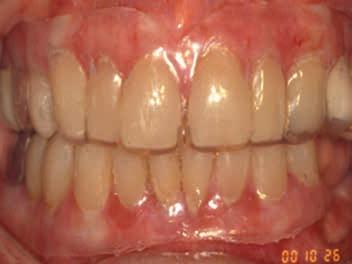

Oral manifestations of pemphigus vulgaris include bullous lesions, erosions with ragged borders, desquamative gingivitis and a positive Nikolsky’s sign (Figures 7,8). Multiple large lesions on the skin can result in fluid loss, electrolyte imbalance, septicemia, and death.

Figure 6. Symblepharon (scar) in a patient with MMP extending from the conjunctiva to the eyeball. Figures 7 and 8. Erosions with ragged borders seen with pemphigus vulgaris. Figure 7 Figure 8